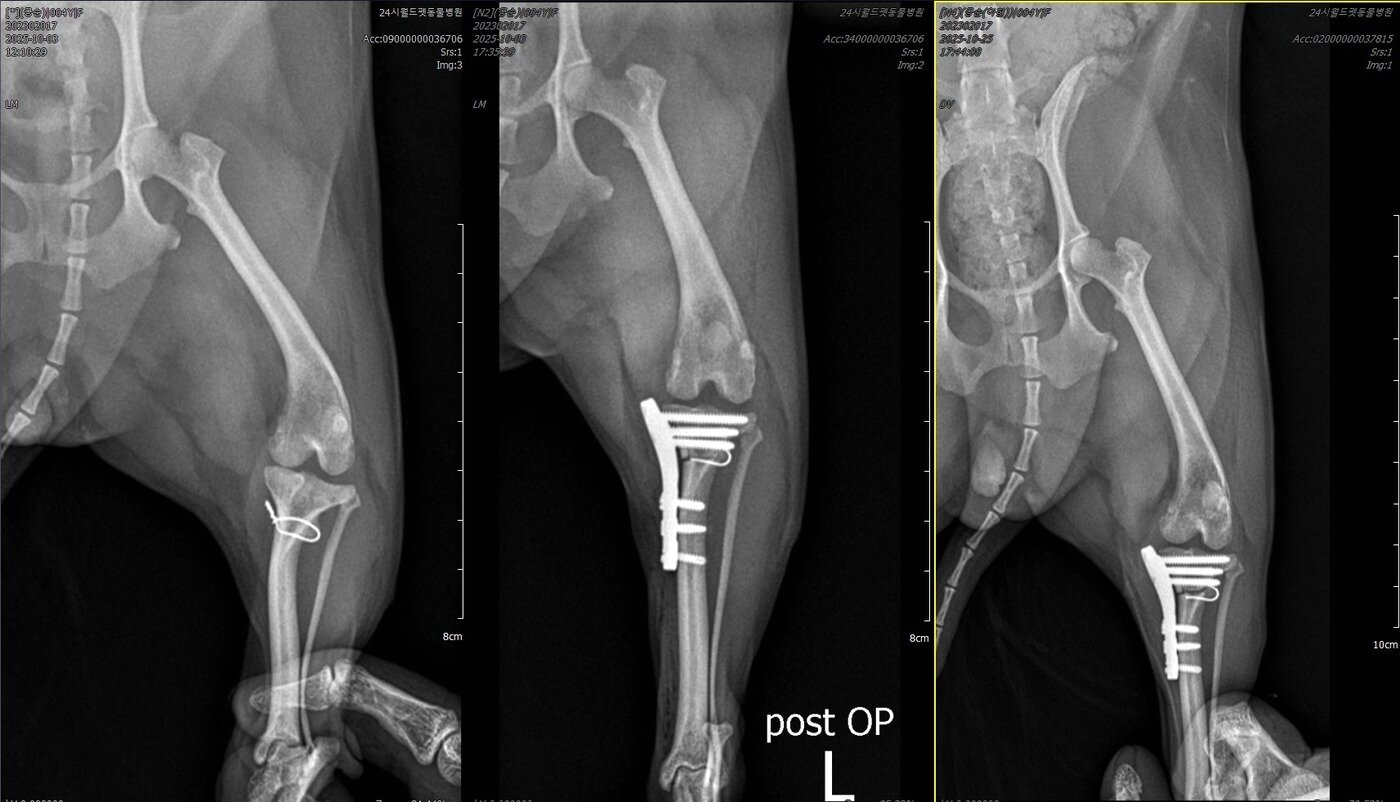

본문 이미지 - 콩순이의 TPLO 수술 전, 후, 최근 방사선 사진(월드펫동물메디컬센터 제공) ⓒ 뉴스1

콩순이의 TPLO 수술 전, 후, 최근 방사선 사진(월드펫동물메디컬센터 제공) ⓒ 뉴스1